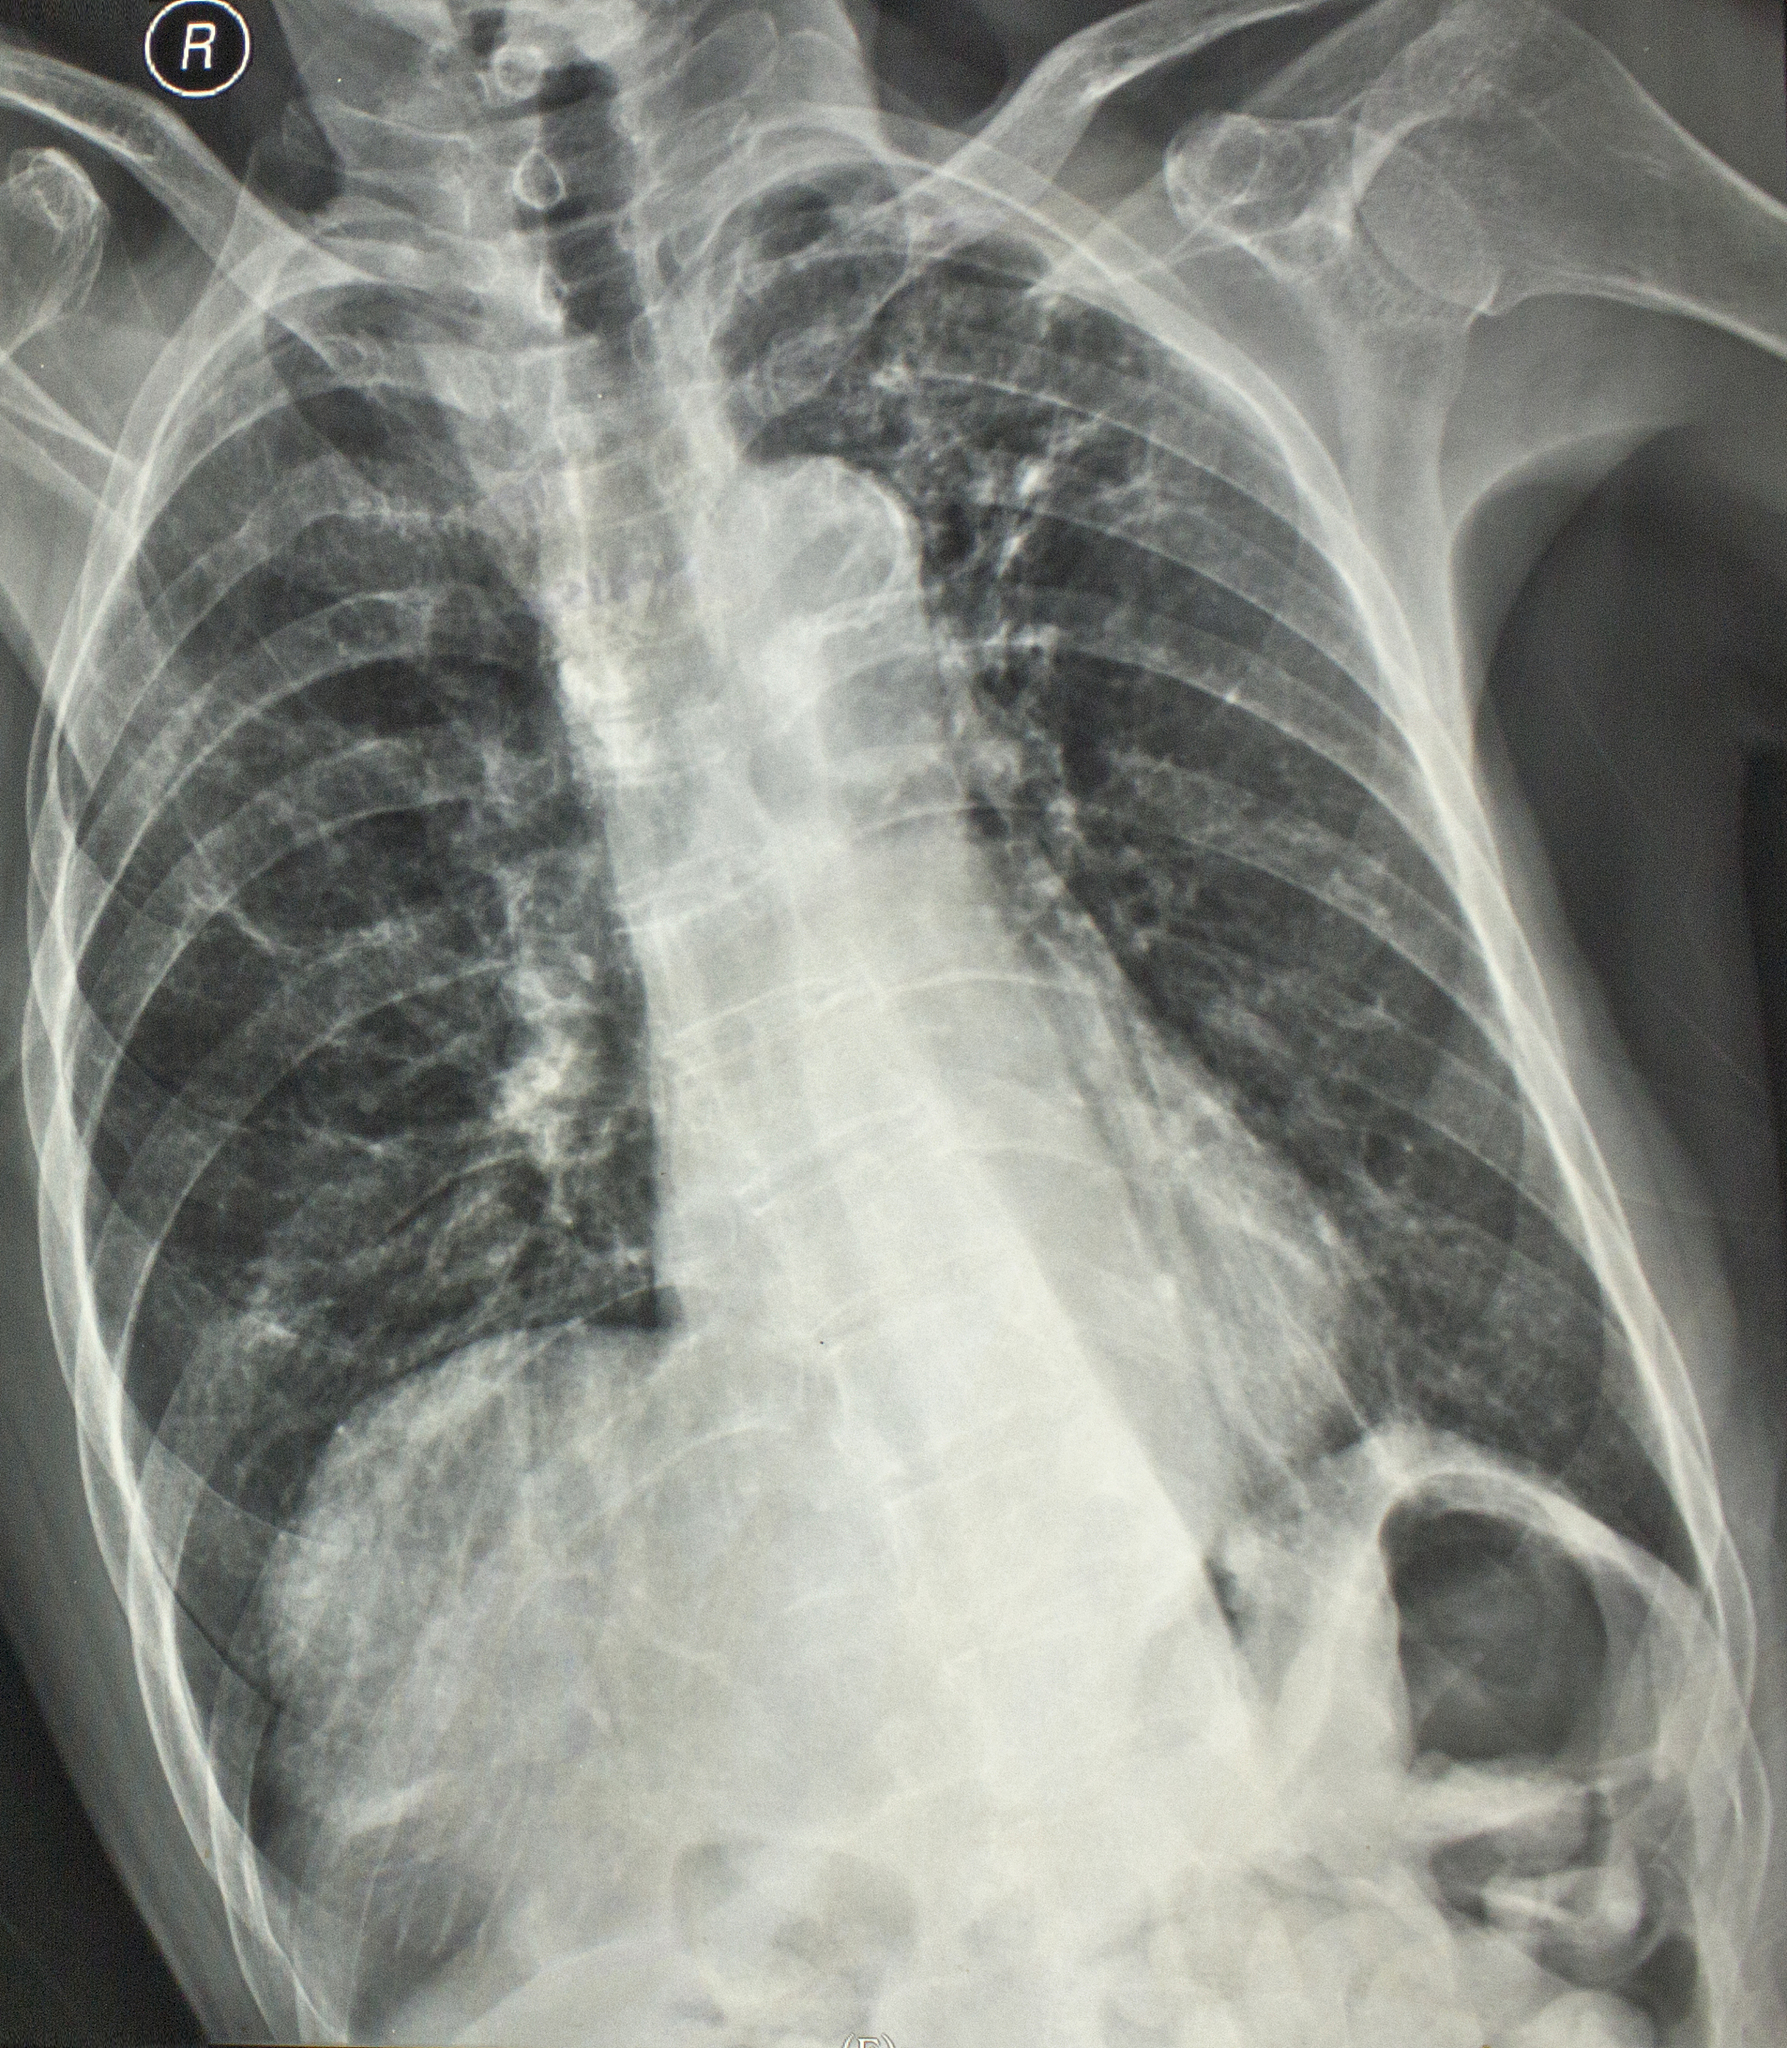

在进行X线胸片体检时,如果发现胸片上有小结节,医生通常会建议进行CT检查。这是为什么呢?我们知道,胸部摄片的原理是将胸壁软组织、骨骼、肺部和心脏大血管投影在一张胶片上。然而,纽扣、衣物上的饰物、乳头影、皮肤疣、肋骨骨岛等因素都可能造成肺部小结节的假象。为了区分是真正的肺部小结节还是这些假象,需要进行胸部CT检查。\n\n胸部CT的原理是将物体切成许多薄片,一层一层地剖开来观察内部结构,因此不存在重叠伪影的问题。上述的纽扣、衣物上的饰物、乳头影、皮肤疣、肋骨骨岛等可以清晰地区分开。胸部CT检查能够明确发现肺部小结节,确诊肺部小结节病灶。